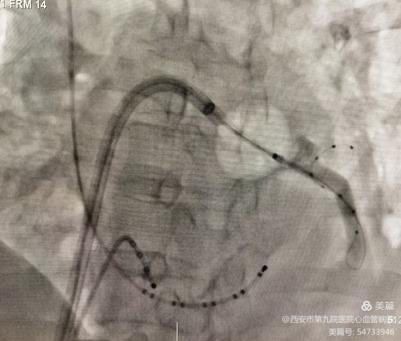

冷冻后验证肺静脉隔离完全。冷冻消融大约持续1小时顺利结束。继之进行左心耳封堵术。左心耳造影测量深度及基底部宽度:

根据造影结果,选择了匹配封堵器,并沿鞘管将封堵装置推送至左心耳内,在食道超声引导下精准定位符合”PASS”原则完成 Watchman 封堵器的释放。封堵后左心房造影显示未见明显残余漏,手术过程均非常顺利。